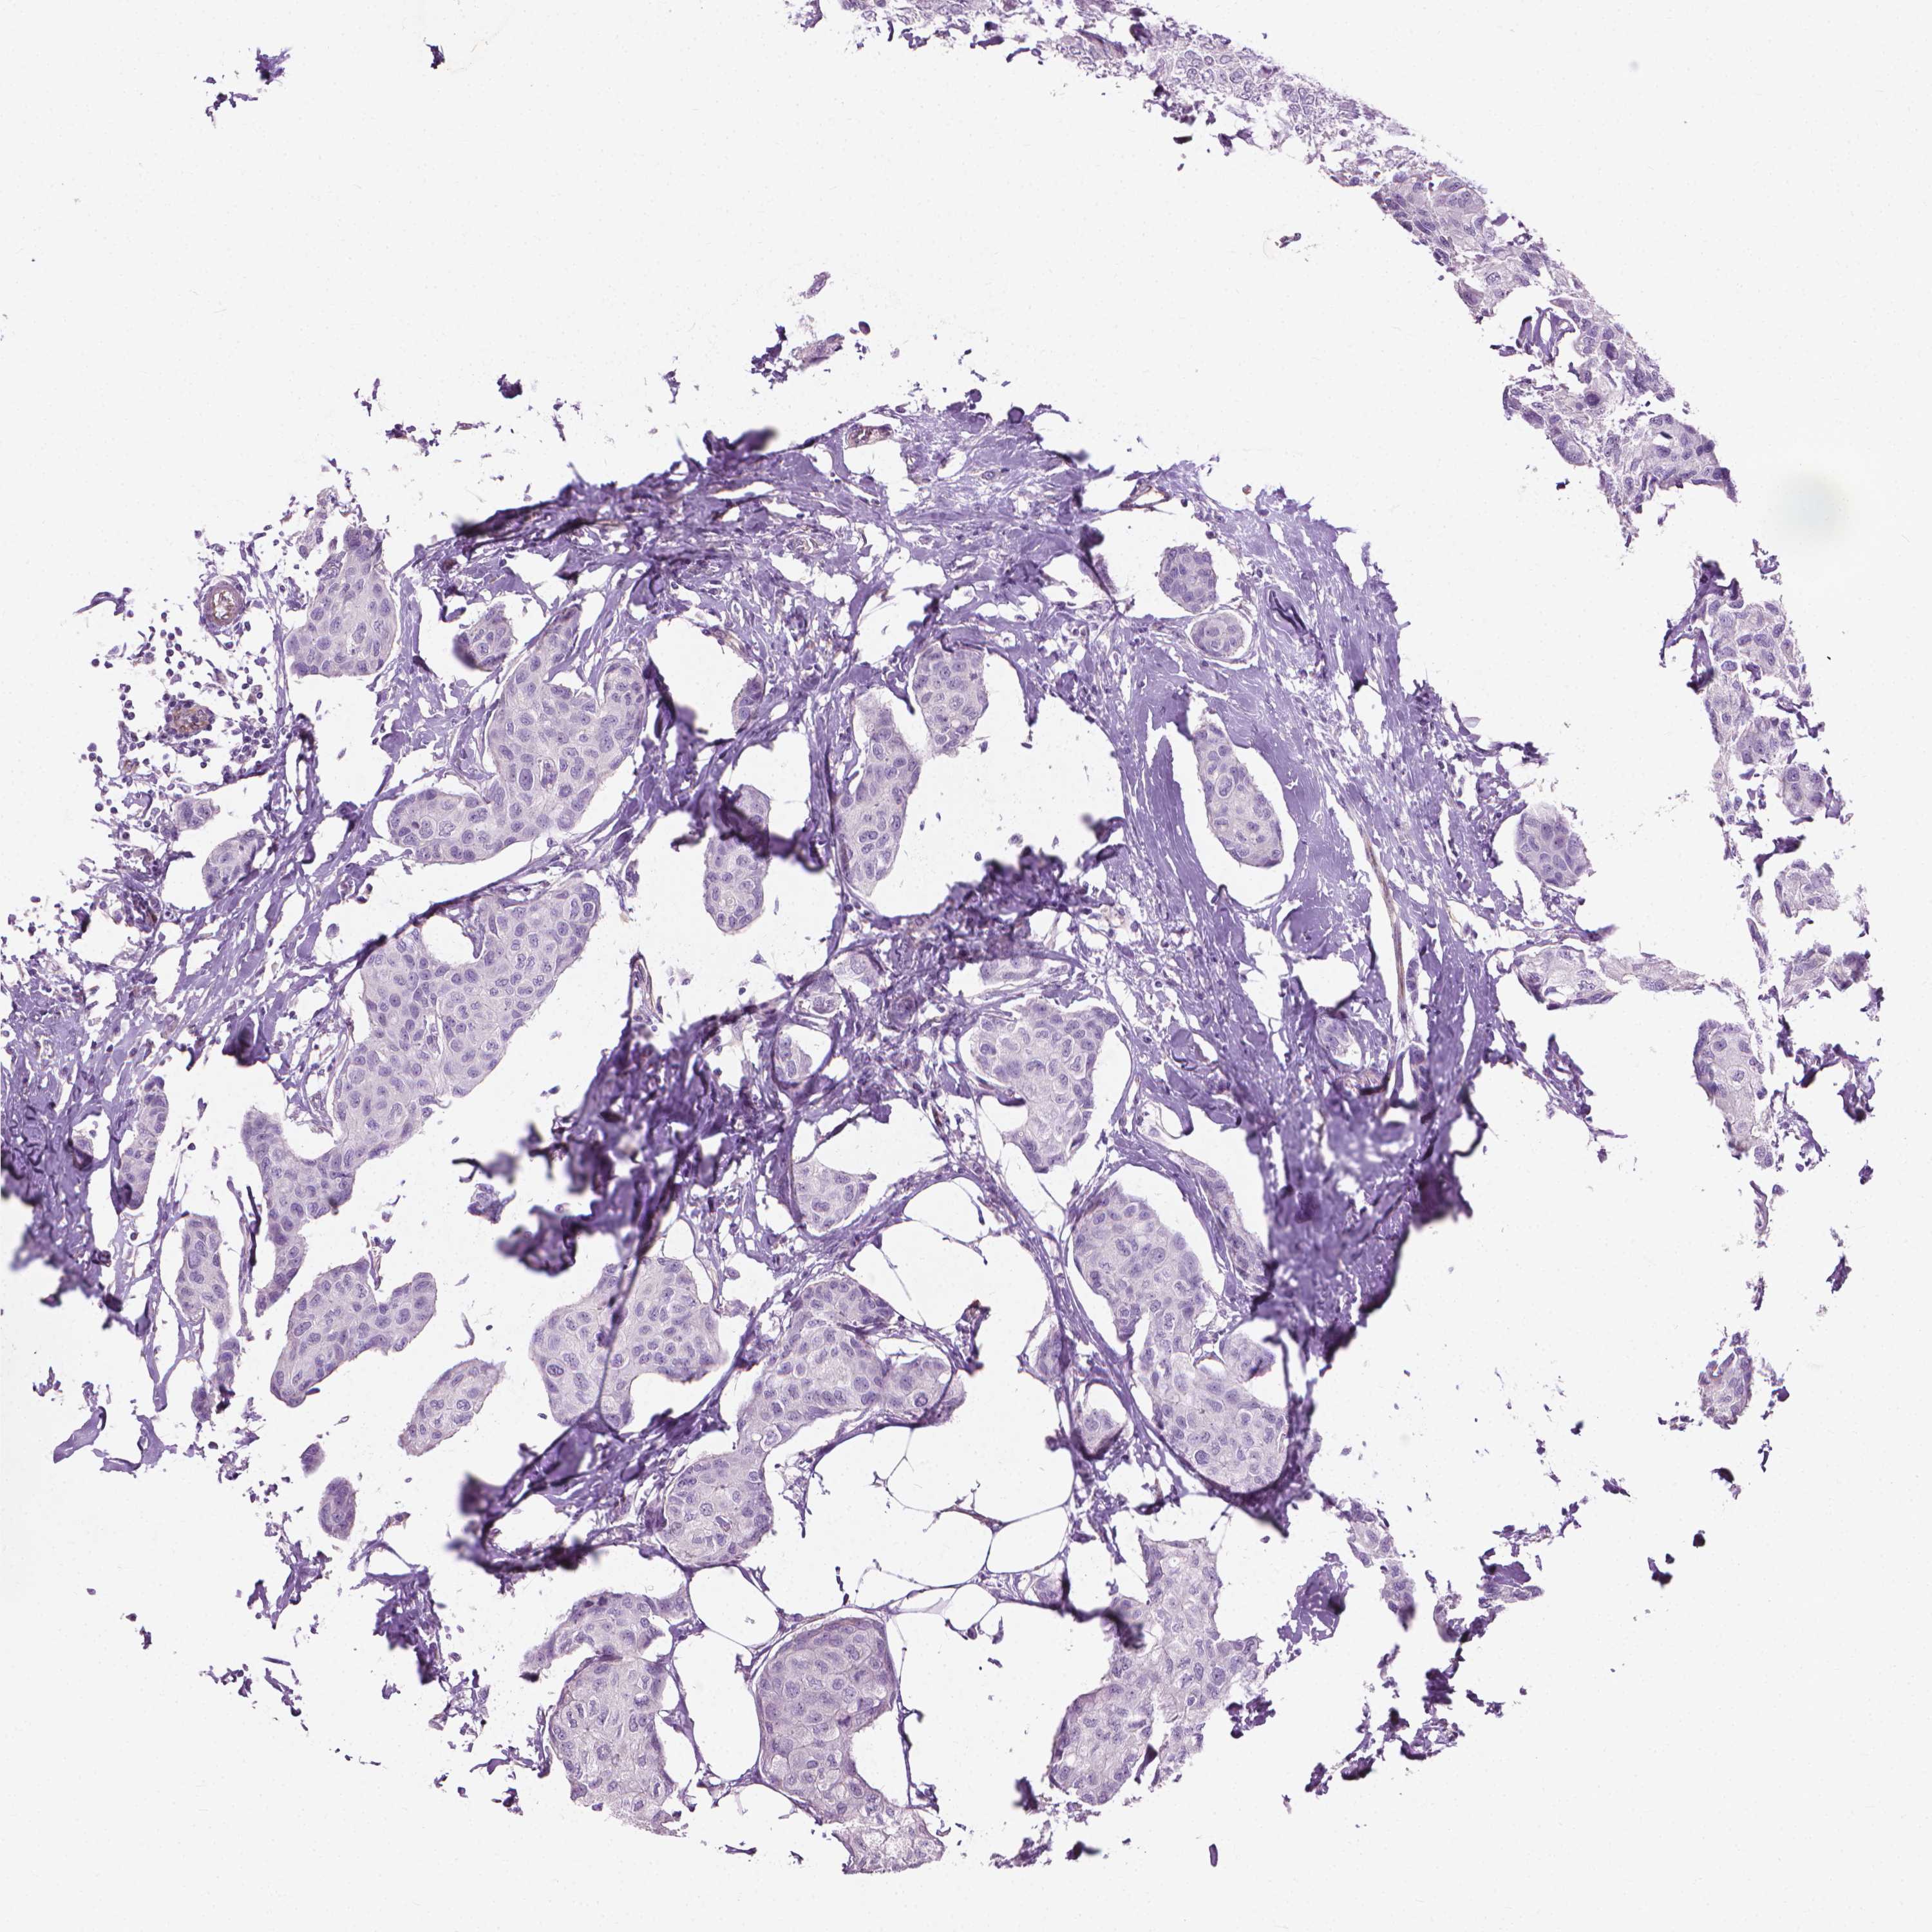

BRCA TCGA BRCA VALIDATION PROTEIN EXPRESSION